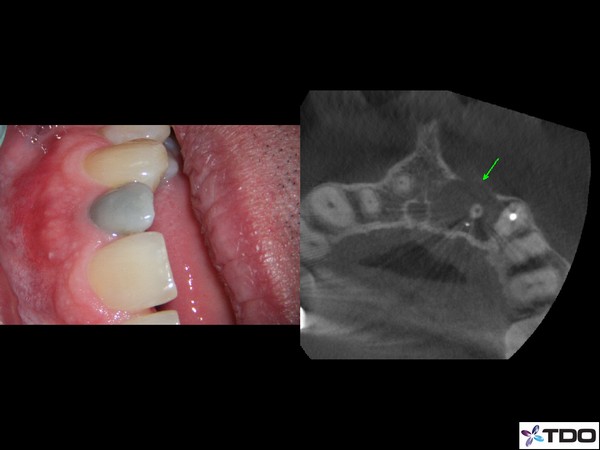

Bleaching and Healing

A root canal infection can cause tooth discoloration and a tremendous amount of bone loss.  The tooth can be effectively bleached.  With careful treatment, we can predictably get the bone to heal.